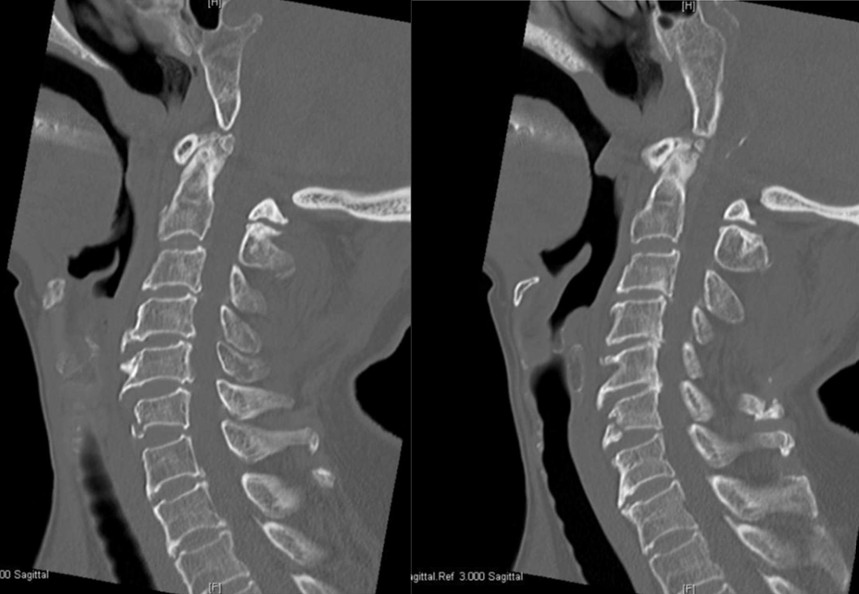

An 87-year-old lady from home presents after a slip and fall down her stairs. She has significant neck β¦

Start Case